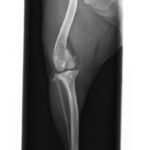

左が正常な膝関節X線写真、右が前十字靭帯が断裂した膝関節のX線写真です。分かりづらいかと思いますが、右の膝関節の方が下の骨(脛骨)が前方に出ていることが分かります。